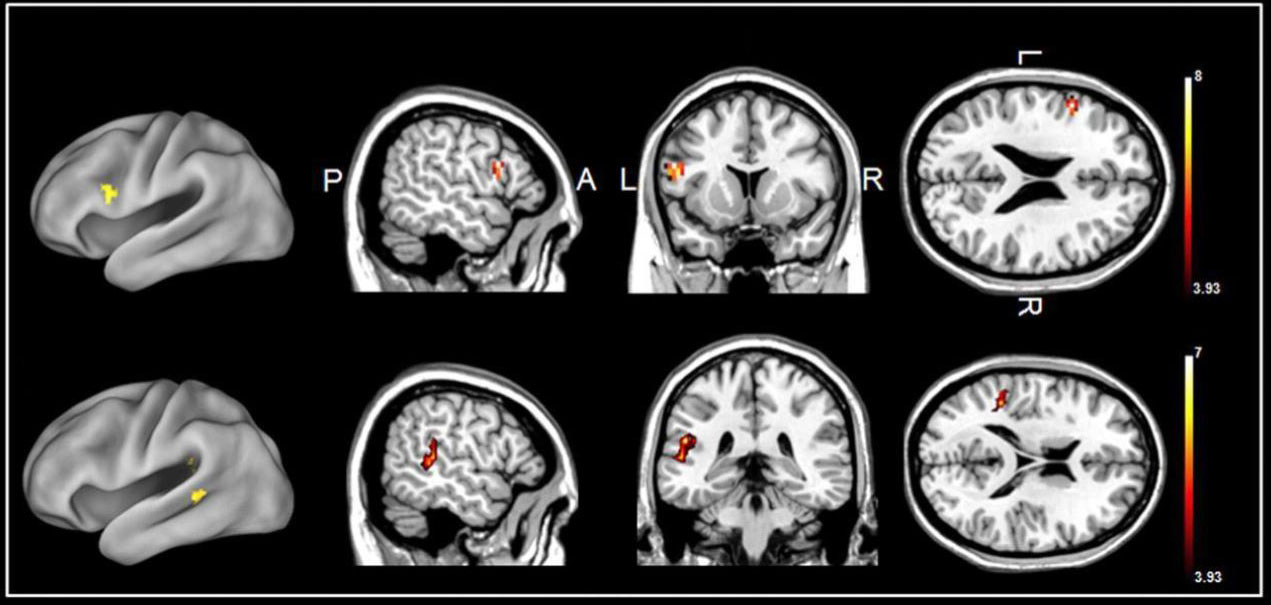

maschio-e-femmina-commettività

Sopra, cervello maschile; sotto, cervello femminile. In blu le connessioni che si sono sviluppate tra aree dello stesso emisfero; in arancione, tra aree di emisfero diverso. Immagine tratta da Sex differences in the structural connectome of the human brain Ragini Verma et al, University of Pennsylvania, PNAS, n ovembre 2013.

Lo studio da cui sono tratte queste immagini ha dimostrato che i maschi sono più connessi all’interno di ciascun emisfero, le femmine tra i due emisferi.

Il che grosso modo significa che i maschi si specializzano verso l’integrazione tra movimento e percezione, mentre le femmine tra logica e intuizione.

Possiamo anche notare che le connessioni tra emisferi sono quasi soltanto nella parte anteriore del cervello. Infatti sono totalmente assenti nel cervelletto.